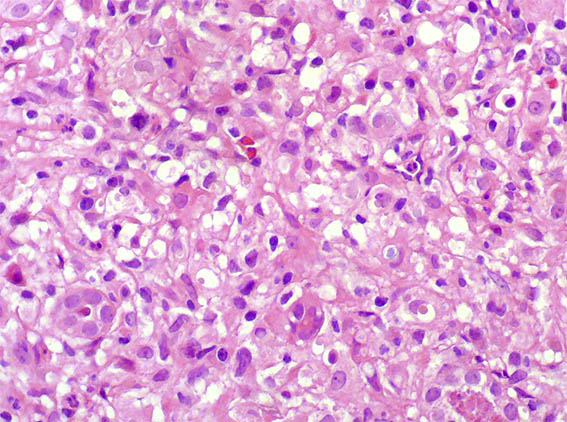

Figure 3. H&E, X400.